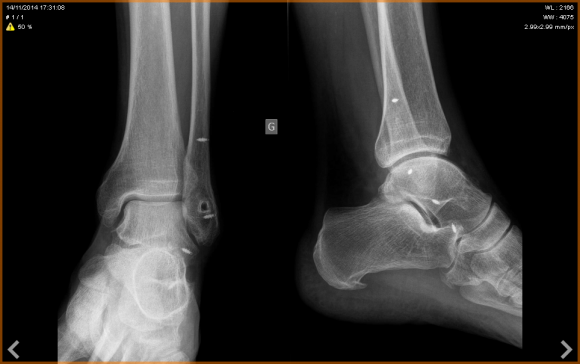

ch'ti lillois d'vizille a écrit:Voilà, le verdict radiologique du pied est tombé ce soir:

- énorme inflammation au niveau de l'insertion de l'aponévrose sur le talon avec une très belle épine calcanéenne en forme de griffe d'aigle....

- pas de constatation de fracture de fatigue sur les métatarses mais par contre un rdv est pris pour le 9/12 afin de faire une IRM du pied afin de comprendre pourquoi le pied ne déroule pas correctement.

Donc, plutôt que d'espérer une possible guérison miracle d'ici 3 semaines (une épine calcanéenne ne disparait pas sans intervention), ni le reste autant déclarer forfait et laisser la place à un participant valide.

Cette décision est grosse sur la patate, mais faut savoir accepter, se guérir et mieux revenir.